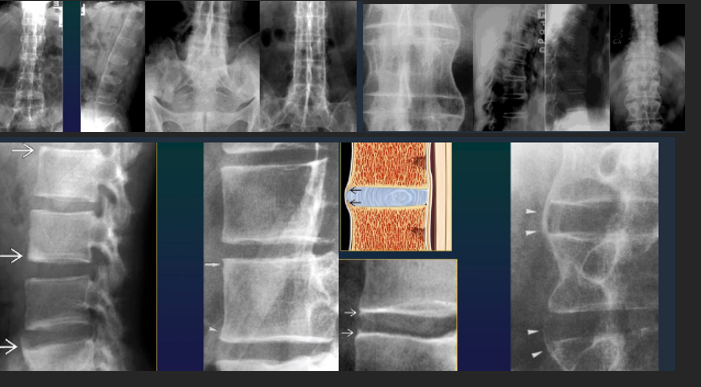

Spondylolisthesis + Spondylolysis

Spondylosis

Osteophytosis

any segment, at 1st horizontal, then vertical

McNab Osteophyte

Discarthosis

narrowing, bulging, vacuum phenomen

OS

Intraspongious hernias (schoolroom nodules)

Disk calcification

Spine

Spondylotis

Arthrosis of small posterior joints

Spondylarthrosis

Uncarthrosis

Arthrosis Rx

GENERAL Rx signs

Joint space narrowing (even or uneven)

Subchondral OS

Subchondral cysts

Osteophytes

Technique: 2 views AP + prophyle

Spine AS

Shiny corners

Square vertebrae

Syndesmophites

Bamboo stick

Calcifications

Interspinate

Yellow lig (tram line)